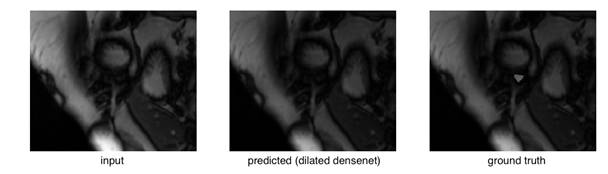

检查异常值时,我们发现它们主要来自右心室难以识别的心脏顶端切片(靠近底部尖端)。 这是验证集上扩展densenets的所示异常值:

右心室在原始图像中几乎看不到,真实值的面积也相当小。将其与比较成功的分割比较:

或者简单的情况比较: